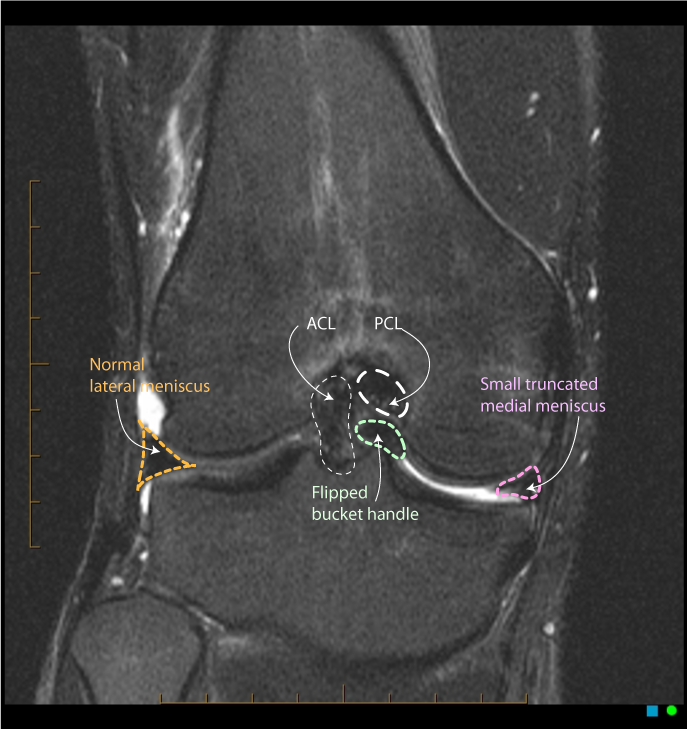

11. 양동이 손잡이형 파열(Bucket-handle tear)이란 무엇인가? MRI 상의 형태를 기술하라.

양동이 손잡이형 파열(Bucket-handle tear)은 외상성 파열의 아형으로 전체 반월판 파열의 10%를 차지한다. MRI는 대개 다음과 같이 보인다. (1) '나비 넥타이 부재 징후(Absent bow tie sign)'로 알려진 나비 넥타이와 닮은 내부 몸 분절(body segment)의 부재와 (2) 전이성 반월판 파편의 존재가 관상면 영상 상 과간절흔에 위치하여 이중 후방십자인대 징후(Double PCL sign)라고 하는 두번째 후방십자인대처럼 보인다.

△ 이중 후방십자인대 징후 (Double PCL Sign)

(이미지 출처 : http://radiopaedia.org/articles/double-pcl-sign)